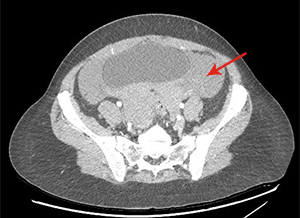

There is a large hemoperitoneum (arrow below) with a massive rectouterine structure (star below) concerning for clot.

We were most concerned about a ruptured ovarian cyst as the patient’s pregnancy test was negative and there was no other obvious cause of blood in the abdomen. She did not have the classic story of onset of pain after intercourse. We did a CT scan because the bedside ultrasound images were difficult to interpret due to the clotted blood. The radiologist suspected ruptured ovarian cyst as the cause of the hemoperitoneum.

This patient developed hypotension in the ED her hemoglobin dropped 2.5 points in 2 hours. She was taken urgently to the OR and had 1 liter of blood removed. She was discharged in stable condition later that day.